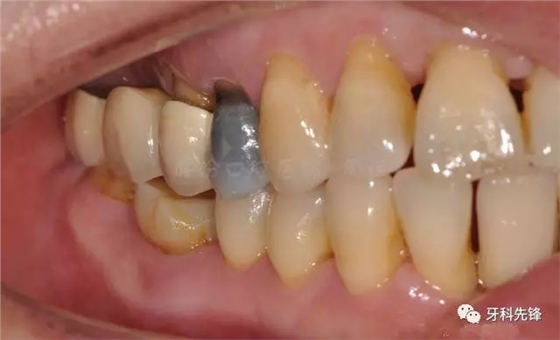

圖2 術(shù)前側(cè)位咬頜照

圖5拆除原修復(fù)體側(cè)位咬合照